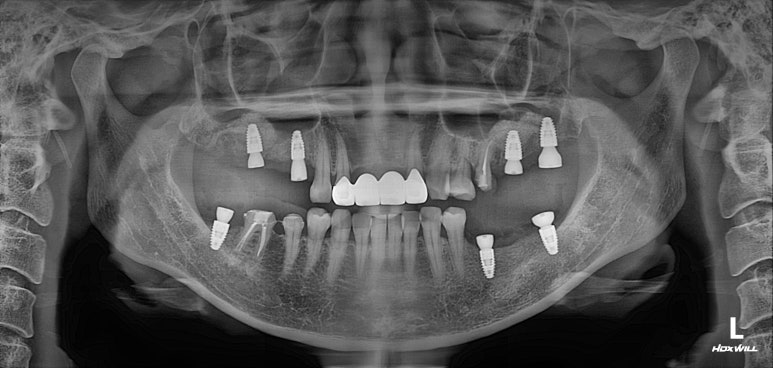

대부분의 수술은 위턱부터 시작합니다.

상악동 뼈이식술을 하면서 임플란트 수술을 시행하였습니다.

왼쪽 위 어금니에 2개, 오른쪽 위 어금니에 3개 총 다섯개의 스트라우만 임플란트를 사용하였습니다.

제 포스팅을 많이 보신 분들은 아실텐데, 상악동 뼈이식술도 함께 진행하였습니다.

내원했을 당시 처음과 비교해보면, 노란선으로 표시된 상악동 뼈이식술 라인을 관찰하실 수 있을겁니다.

상당히 깔끔하게 수술이 이뤄졌네요!

그리고 저희 치과는 치과보존과 전문의 원장님이 함께 계신데, 주황색으로 표시된 두 치아가 깔끔하게 신경치료가 마무리 된 것을 보실 수 있습니다.

위턱 임플란트를 심어드리고 3주 뒤에 아래턱 임플란트를 심었습니다.

오른쪽 아래 어금니에 2개, 왼쪽 아래 어금니에 1개 (그리고 사랑니 발치까지) 수술이 잘 이루어졌네요!!

그렇게해서 최종완료 후 치과용 파노라마 사진입니다!

치과치료에 대해 잘 모르시는 분이라 할지라도 보고 있으면, 치료가 조화롭게 잘 끝났구나.. 라고 아실 수 있으리라 생각합니다.

제가 제일 좋아하는 치과용 파노라마 비교 사진입니다.

앞으로 나란히를 한 것 같이 평행한 임플란트의 완성도는 항상 카타르시스를 느끼게 합니다.